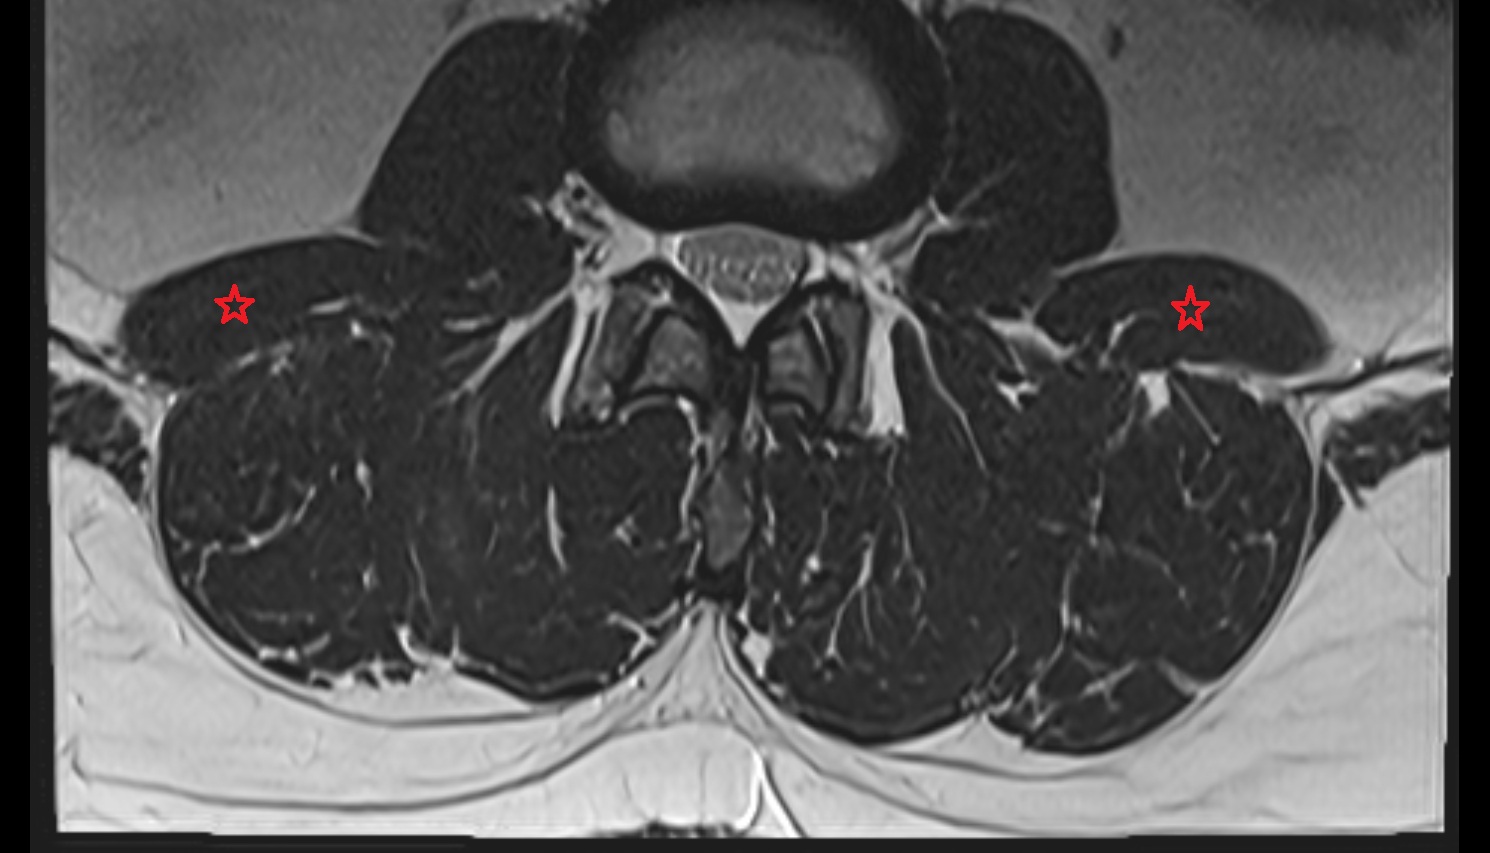

- Cauda equina